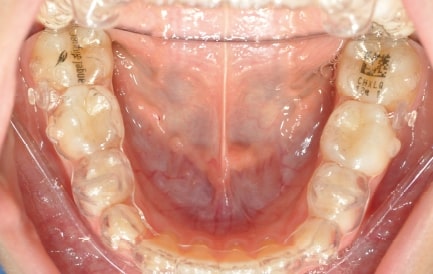

Malocclusion A6 Correction of Mandibular Retrusion in Growth phase patient | Skeletal Class II | Class II Division 1 malocclusion | Deep bite | Mixed dentition

- Upper Archform enlargement (dental expansion)

- Normalize Overjet/Overbite (Lower Posterior Extrusion)

- Alignment/Leveling Both Arches

AngelAligner KiD 1 (aligners changed every 10 days)

Treatment setup

Treatment progress